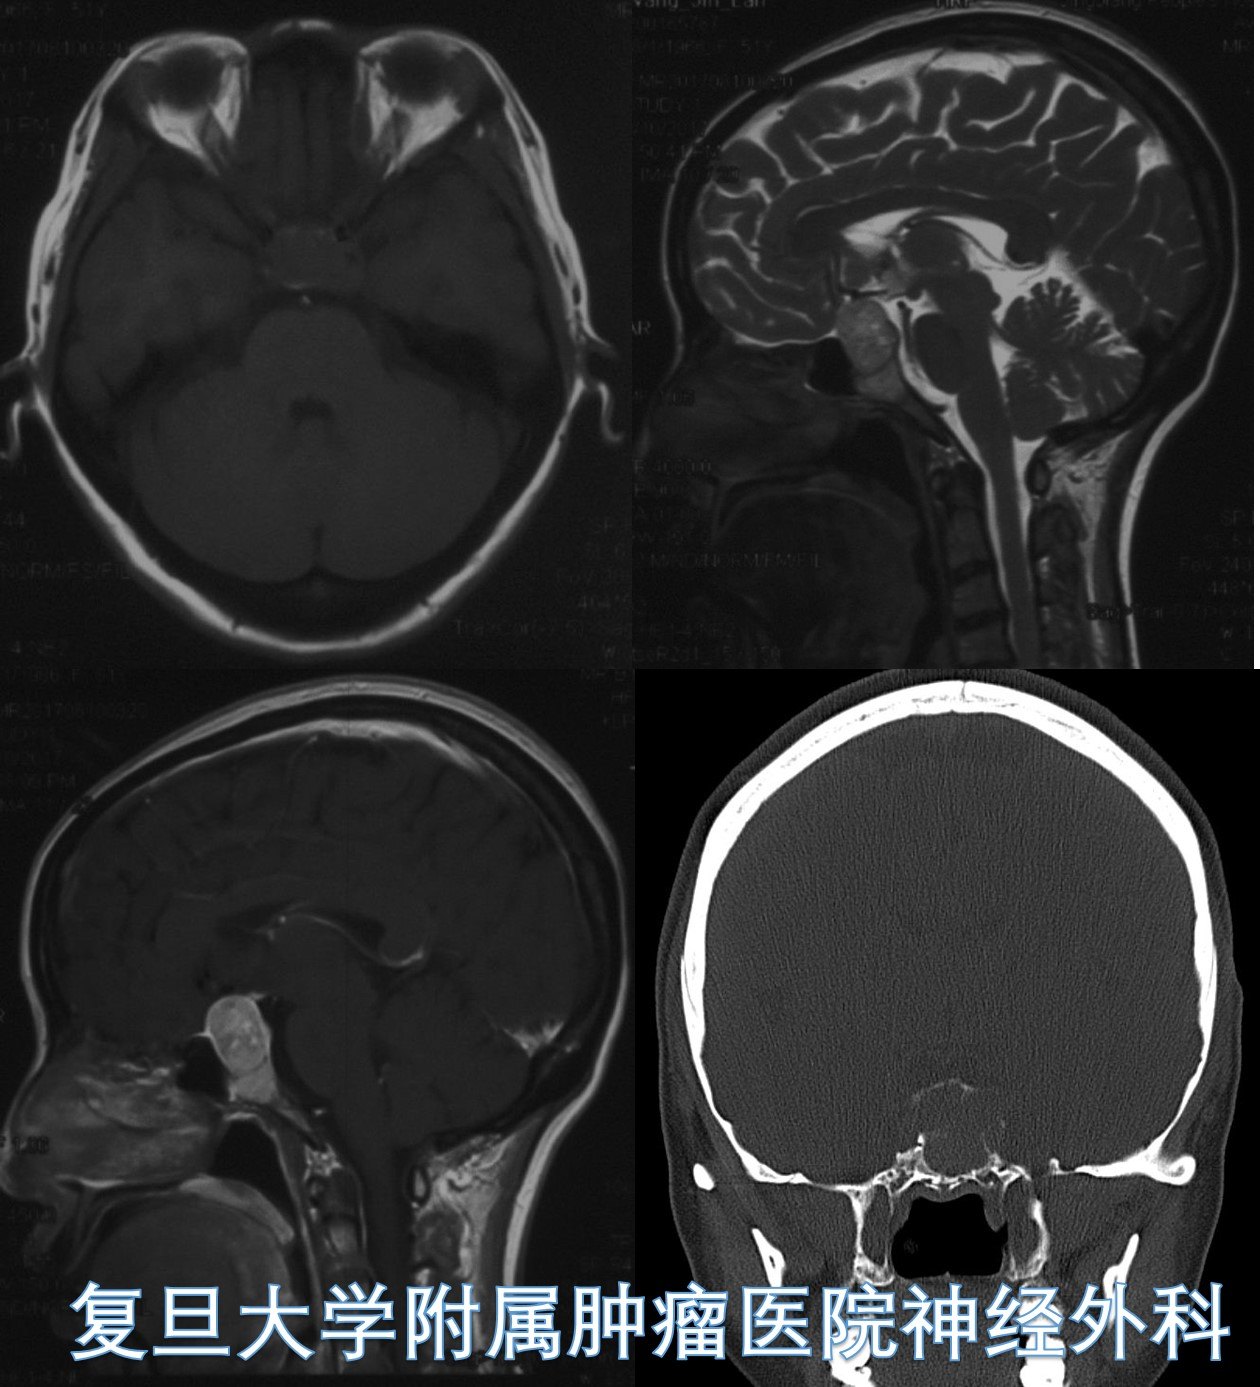

Case 1复旦大学附属肿瘤医院神经外科高阳

女,39岁,头痛头晕1年余。

鞍区增强MRI示:鞍区可见异常占位性病变,肿瘤大小约3cm,鞍底、斜坡受侵犯,双侧海绵窦被包饶。T1WI示等信号,T2WI示混杂高信号,增强可见中度强化。病变与正常垂体组织似有一定边界,斜坡硬膜受压。

冠状位CT示:鞍区病变,肿瘤无钙化,斜坡骨质受侵犯破坏。

术后病理提示:脊索瘤。